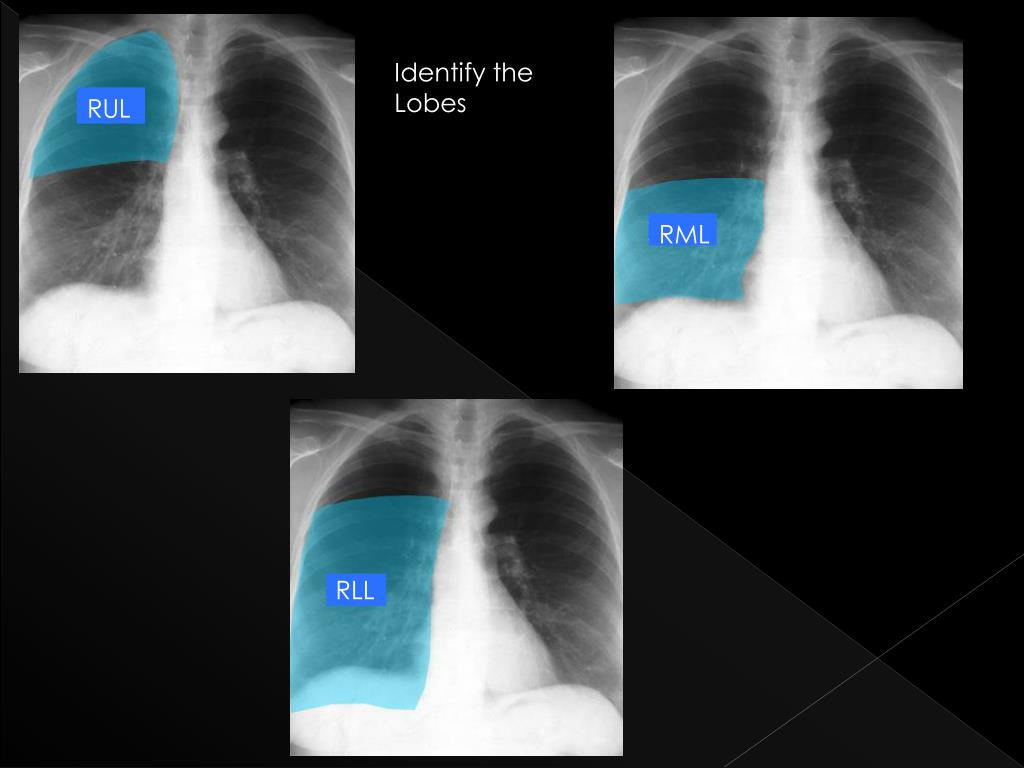

23. Identify the Lobes

24. Identify the Lobes LUL LLL

25. Identify the Lobes

26. Identify the Lobes RUL RML RLL